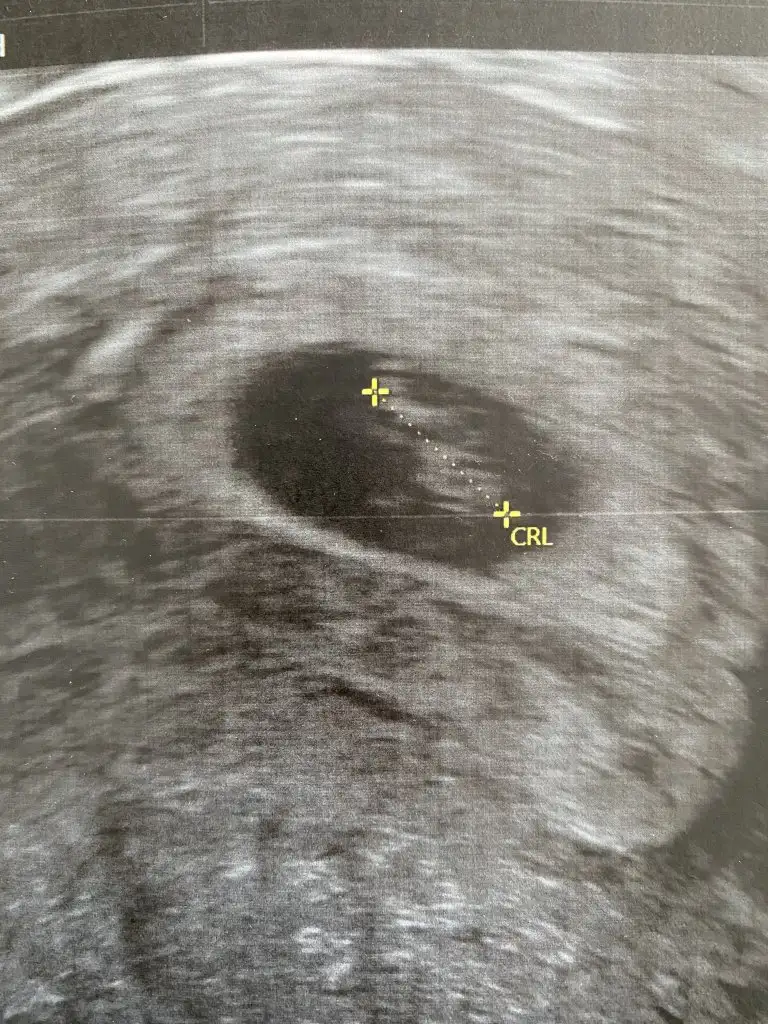

Kız sanki emin olamadım 13 hafta USG olursa paylaşınEki Görüntüle 2777828 11+5 tahminlerinizi alabilirsek çok seviniriz, çok merak ediyoruz![]()

14 +0 hafta hanımefendi. Doğru pozisyona tam gelmedi baya kıpır kıpırdı hep döndü durdu. en alınabilir görüntü bunlar malesef. bi dahakine zaten öğrenmiş olurum heralde. yinede saolun.Kız sanki emin olamadım 13 hafta USG olursa paylaşın